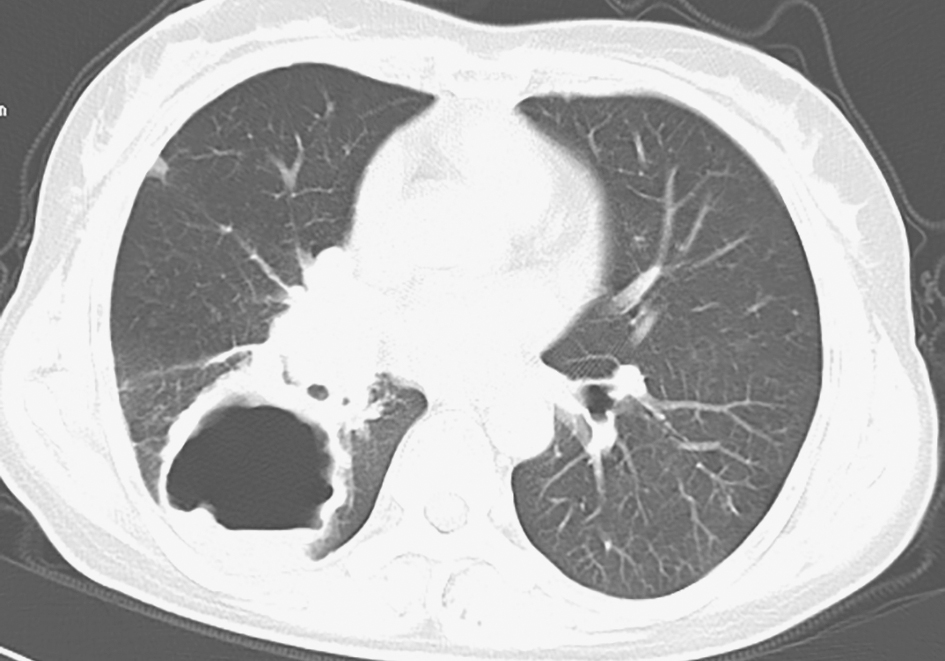

图5 肺曲霉菌病胸部CT表现

胸部CT见双肺多发空洞,左肺空洞内可见曲霉菌球

图6 肺隐球菌病胸部CT表现

胸部CT见双肺多发结节影,其内可见小空洞,右下肺近胸膜处空洞明显

包括球孢子菌病、肺曲霉菌病、肺隐球菌病等,可导致肺部空洞形成,但胸部CT影像学表现缺乏特异性。典型的肺曲霉菌病可表现为晕征、空气新月征、曲霉菌球(图5);肺隐球菌病可出现肺实变、肿块及胸膜下结节影,其内可出现空洞(图6)。